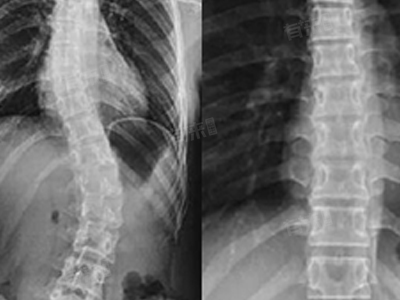

- 较常见的是X光片检查,它主要用于初步观察骨骼形态,价格相对较低。一般来说,手部、脚部等小关节部位的X光片费用通常在50元到150元之间。而脊柱、骨盆等结构复杂且重要部位的X光片,因拍摄需要更精确的定位和技术,价格可能在150元到250元左右。